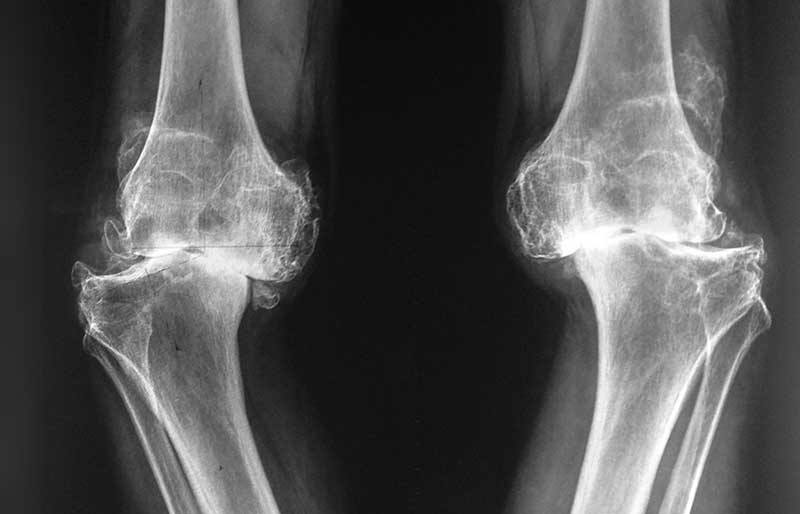

Operasi penggantian sendi lutut adalah suatu operasi untuk mengganti sendi lutut yang rusak akibat osteoartritis (penipisan tulang rawan) dengan sendi buatan yang disebut prosthesis. Penyebab utama kerusakan sendi lutut adalah osteoartritis (baca pen- jelasan tentang “Osteoartritis”) dan sendi yang paling sering terserang osteoartritis adalah lutut.

Operasi penggantian sendi lutut merupakan pengobatan terbaik untuk osteoartritis lutut stadium 3 dan 4. Ada empat tujuan operasi ini, yaitu menghilangkan rasa sakit sendi yang telah rusak, memperbaiki lingkup gerak sendi yang sebelumnya kaku dan terbatas, mengembalikan kemampuan penderita melakukan aktivitas harian tanpa rasa sakit, dan meningkatkan kualitas hidup sehingga penderita kerusakkan sendi dapat menjalani hidup secara aktif bebas dari nyeri sendi.